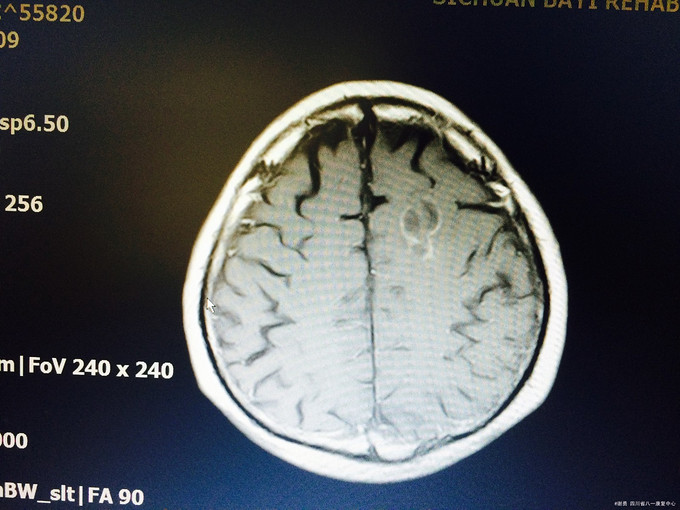

入院查体:生命体征平稳,高级皮层功能正常;四肢肌张力不高,肌力5级,病理征未引出;头颅MRI示:左侧额叶皮层下见23*15*16mm“多囊状”异常信号,见等信号囊壁,周边少许水肿信号,增强信号见病灶壁环形强化,边缘一结节状强化,肿瘤?脑囊虫病?左颞叶、顶叶、颞叶多个结节状,长T1长T2信号,FLAIR呈高信号;左颞叶见一强化“小结节”; 入院诊断:颅内占位改变,性质待定:脑膜瘤?脑囊虫病?

颅内占位疾病,定性诊断是难点:本疾病考虑脑囊虫病的支持点:亚急性起病,影像学上发现多囊状异常信号,囊壁环形强化,脑脊液提示炎性反应,不支持点寄生虫全套为阴性,但仍然需诊断性治疗;脑膜瘤,强化不支持;血管瘤?需进一步追踪、随访。